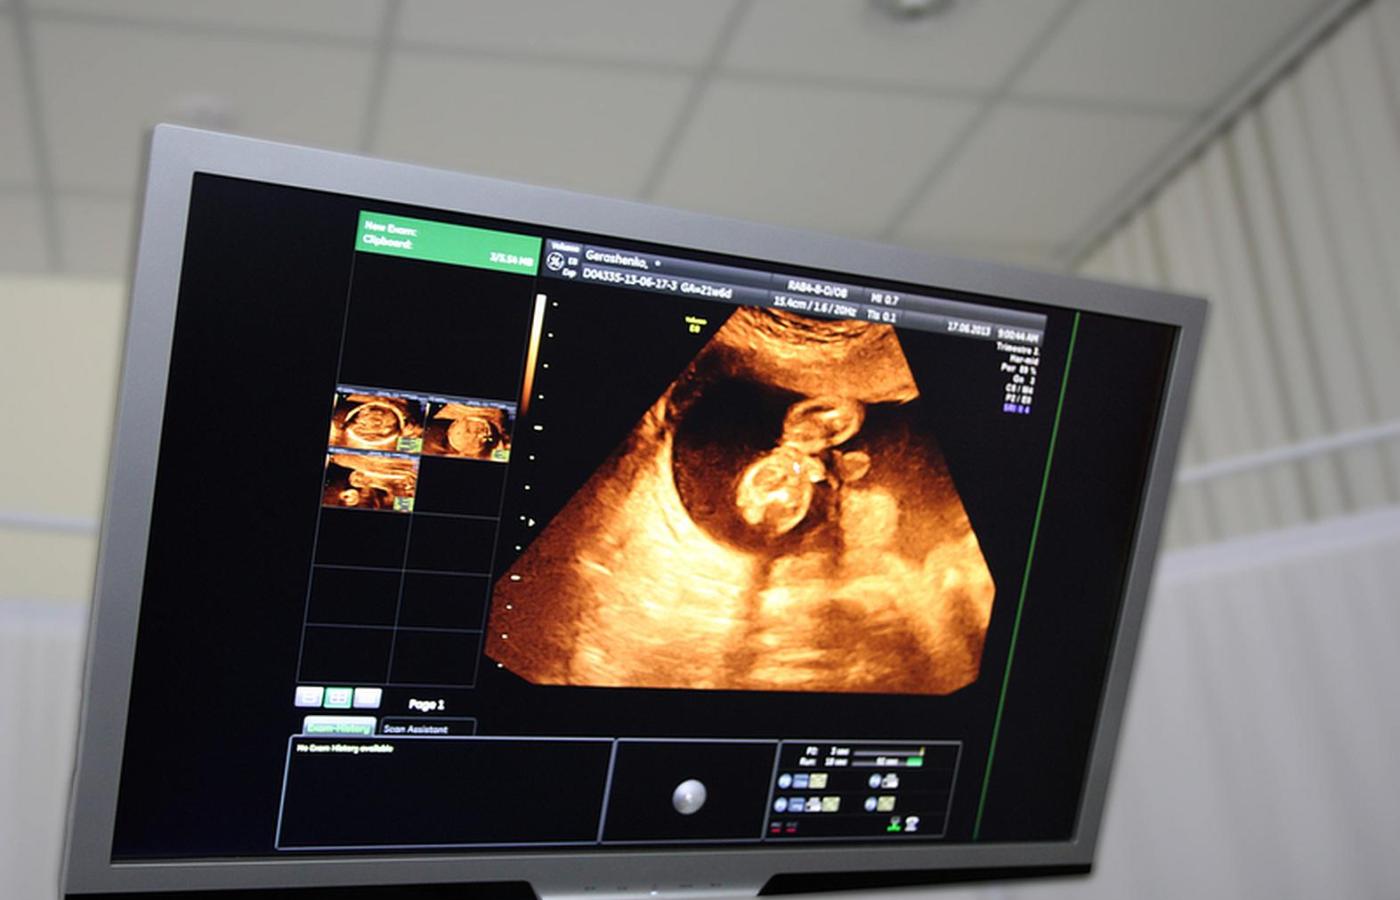

Na Islandii badania prenatalne są darmowe. Odbywają się one w formie testu kombinacyjnego: badanie krwi oraz ultrasonografia.Kostia777/Smarterpix/PantherMedia Na Islandii badania prenatalne są darmowe. Odbywają się one w formie testu kombinacyjnego: badanie krwi oraz ultrasonografia.

Na Islandii badania prenatalne są darmowe i lekarze muszą o nich poinformować ciężarne. Odbywają się one w formie testu kombinacyjnego: badanie krwi oraz ultrasonografia. Według rzecznika Szpitala Uniwersyteckiego w Rejkiawiku na test decyduje się ok. 85 proc. kobiet w całym kraju. Z tej grupy w przypadku stwierdzenia zespołu Downa od trzech lat wszystkie badane wybierają aborcję.